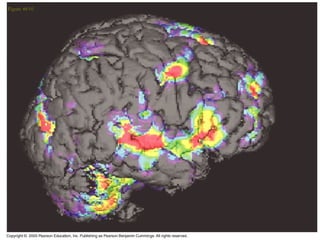

 Las tecnologías recientes, que pueden registrar la actividad

encefálica desde el exterior del cráneo de una persona.

 Una técnica es la resonancia magnética funcional (RMf).

 Durante la RMF el individuo está acostado con la cabeza

dentro de un gran imán con forma de “rosquilla” que

registra el aumento del flujo sanguíneo en las áreas

encefálicas con neuronas activas.

 Un ordenador utiliza los datos para construir un mapa

tridimensional de la actividad cerebral del individuo.

 Estos registros se pueden hacer mientras el individuo

realiza varias tareas, como hablar, mover una mano,

observar dibujos o formar una imagen mental de un objeto

o del rostro de una persona.

CENTRO DE MANDOY CONTROL  Las tecnologías recientes, que pueden registrar la actividad encefálica desde el exterior del cráneo de una persona.  Una técnica es la resonancia magnética funcional (RMf).  Durante la RMF el individuo está acostado con la cabeza dentro de un gran imán con forma de “rosquilla” que registra el aumento del flujo sanguíneo en las áreas encefálicas con neuronas activas.  Un ordenador utiliza los datos para construir un mapa tridimensional de la actividad cerebral del individuo.  Estos registros se pueden hacer mientras el individuo realiza varias tareas, como hablar, mover una mano, observar dibujos o formar una imagen mental de un objeto o del rostro de una persona.